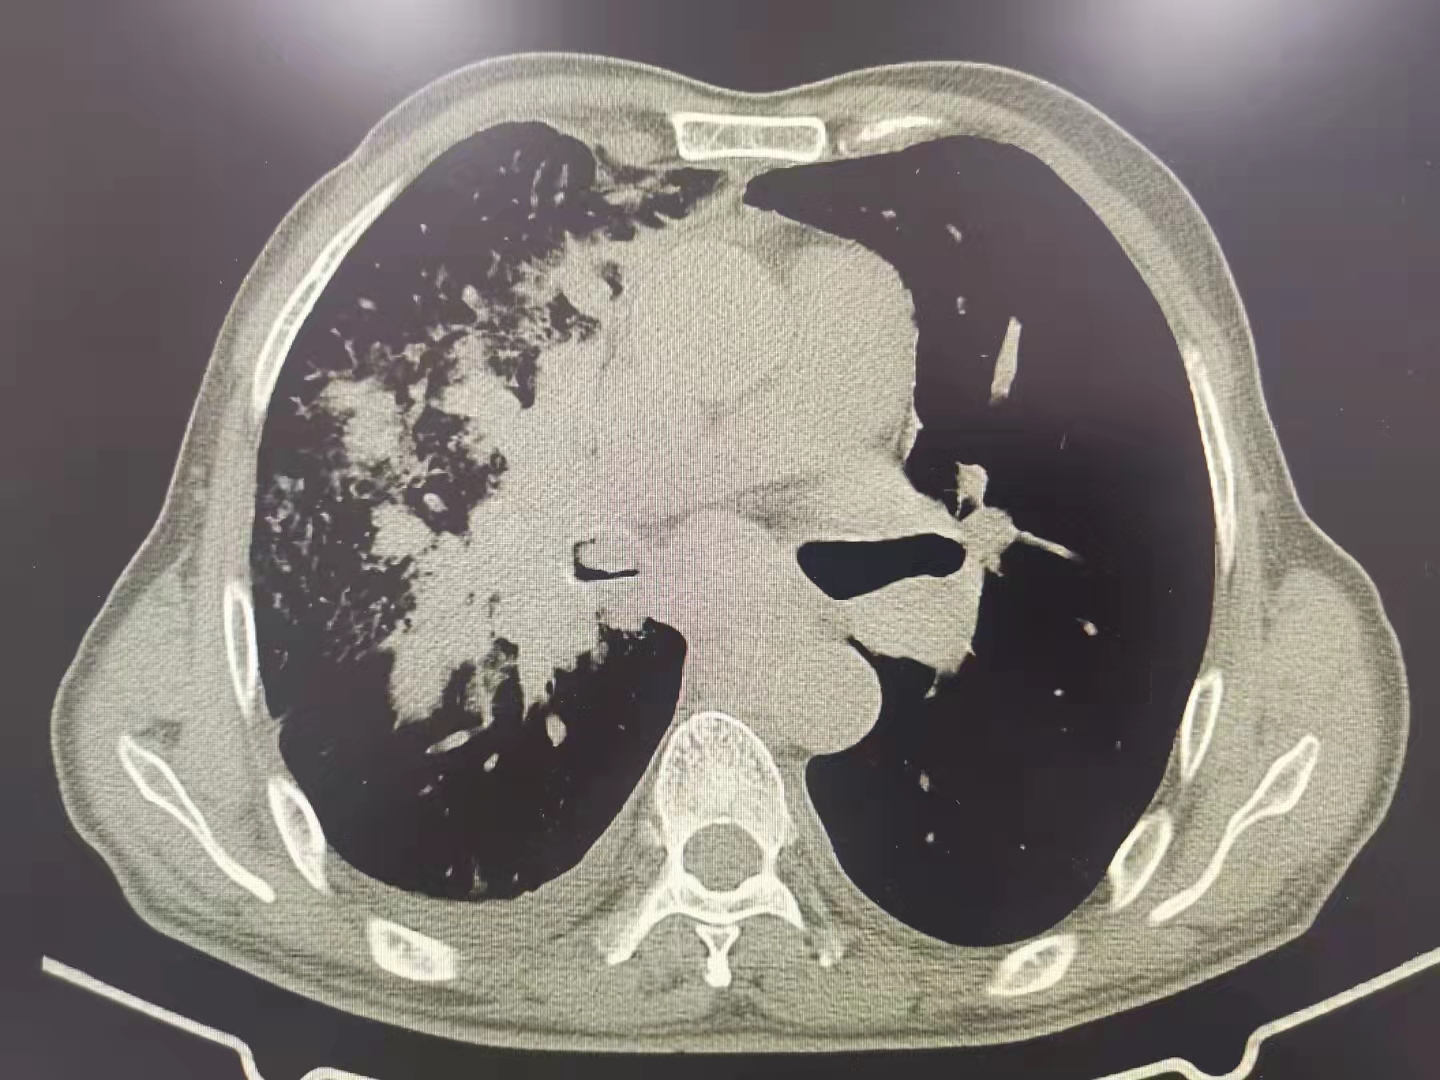

今日再次為一例肺部占位合并氣道內(nèi)腫瘤的患者施行支氣管鏡下的介入手術(shù),術(shù)前呼吸困難、心律失常二聯(lián)律,術(shù)后患者呼吸困難明顯緩解,且心律失常得以糾正,效果立竿見影。但是影像學(xué)的巨大腫塊,還需要結(jié)合病理分型采取恰當(dāng)?shù)木C合治療手段來減緩和控制疾病進(jìn)展。呼吸介入,我們團(tuán)隊一直在前進(jìn)中。